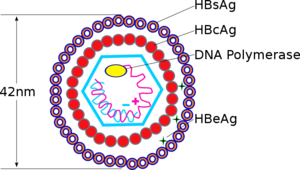

العدوى

يتكون ڤيروس التهاب الكبد الڤيروسي ب، وهو ڤيروس دناوي DNA كبدي من طاقين قطره 42 نانومتر ومن قفيصة منواة (المستضد اللبي) بقطر 27نانومتر، وتحاط بطبقة بروتينية شحمية خارجية تحتوي على المستضد السطحي HBsAg. وهذا المستضد متغاير مستضدياً: فمن أجزائه مستضد مشترك (يرمز له بحرف a) وزوجان مستضدان متنافيان mutualty exclusive (هي d و y وw (ويضم عدة معينات فرعية)، والمستضد r)، ويؤدي ذلك إلى وجود أربعة نميطات subtypes رئيسية هي: ayr,adr,ayw,adw. ويختلف توزع هذا النميطات جغرافياً. ونظراً لوجود المعين المشتركa فإن الحماية ضد أحد النميطات تضفي حماية ضد النميطات الأخرى، ولم يتبين وجود اختلافات في الملامح السريرية تتعلق بكل نميط. وقد تم تقديم تصنيف بالنمط الجيني على أساس توالي المـادة الجـينية وأصبح هو المعيار: ويصنف ڤيروس الالتهاب الكبدي (ب) حالياً إلى 8 أنماط جينية رئيسية (A-H). وهناك بينة متزايدة على الاختلافات في وخامة مرض الكبد بين بعض الأنماط الجينية لڤيروس الالتهاب الكبدي (ب).

يتبع ڤيروس التهاب الكبد ب فصيلة الڤيروسات الكبدية.[9] جسيمات ڤيروس (الفيريون) تتكون من غلاف خارجي من المادة الدهنية ونيكلوكابسيد ايكوساهيدرال تتألف من البروتين. ويحتوى النيكلوكابسيد على الحمض النووي الڤيروسي وبوليميريز الحامض النووي الذي به نشاط عكس المنتسخة.[10] المغلف الخارجي يحتوي على البروتينات التي تعتبر جزءا لا يتجزأ من المشاركة في ملزمة الڤيروسية، ودخولها حيز، وخلايا حساسة. الڤيروس هو واحد من أصغر الڤيروسات الحيوانية التي يلفها الفيريون يبلغ قطرها من 42 نانومتر، ولكن توجد أشكال متعددة الأشكال، بما في ذلك الأجسام الخيطية والكروية التي تفتقر إلى جوهر. هذه الجسيمات غير معدية، وتتكون من الدهون والبروتينات التي تشكل جزءا من سطح الفيريون، وهو ما يسمى المضادات السطحية (HBsAg)، وتنتج في زيادة خلال دورة حياة الڤيروس.[11]

إن ڤيروس التهاب الكبد HBV) B) هو ڤيروس صغير مضاعف القشرة من فصيلة الڤيروسات الكبدية Hepadnaviridae. للڤيروس مجین DNA genome حلقي صغير ثنائي النطاق -double stranded جزئياً. يحتوي ڤيروس HBV عدة مكونات مستضدية هي والمستضد السطحي لالتهاب الكبد HBsA ) B)، والمستضد اللبي لالتهاب الكبد HBcAg) B)، والمستضد e لالتهاب الكبد HBeAg) B). يعتبر الإنسان المضيف الوحيد المعروف لڤيروس HBV، لكن يمكن لبعض الرئيسيات غير الإنسانية أن تصاب بالإنتان في الشروط المخبرية. إن HBV مرن نسبياً، وقد لوحظ في بعض الحالات بقاء الڤيروس معدياً على السطوح البيئية مدة شهر على الأقل في حرارة الغرفة.

هناك عدة أنظمة (مستضد - ضد) معروفة جيداً مرافقة لإنتان HBV. إن HBsAg والذي دعي سابقاً المستضد الأسترالي أو المستضد المرافق لالتهاب الكبد B هو محدد مستضدي determinant موجود على سطح الڤيروس وهو يتألف أيضأ من جزيئات تحت ڤيروسية subviral كروية وأنبوبية بقياس 22 نانومتر. يمكن كشف HBsAg في المصل بعد 30-60 يوماً من التعرض لڤيروس HBV، ويستمر لفترات مختلفة. إن HbsAg ليس معديا ، وإن الڤيروس الكامل (جزيء دان) هو المعدي فقط. ومع ذلك عندما يكون Hbs Ag موجوداً في الدم، فإن الڤيروس بكامله يكون موجوداً أيضاً، ويمكن للشخص أن ينقل الڤيروس. ينتج الڤيروس HBV كميات كبيرة من HbsAg أثناء عملية النسخ replication. إن المستضد اللبي HBcAg هو اللب البروتيني النووي المحفظي لڤيروس HBV، وهو غير قابل للكشف في المصل بالتقنيات التقليدية، لكن يمكن كشفه في نسيج كبد الأشخاص المصابين بإنتان HBV الحاد أو المزمن. أما المستضد (HBeAg) فهو بروتين ذواب موجود أيضاً في لب ڤيروس HBV، وكشف في مصل الأشخاص الذين لديهم عيارات عالية من الڤيروس، ويشير للعدوى (الإخماج Infectivity) الشديدة.